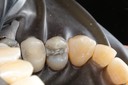

Chris Woo #3 pre-op